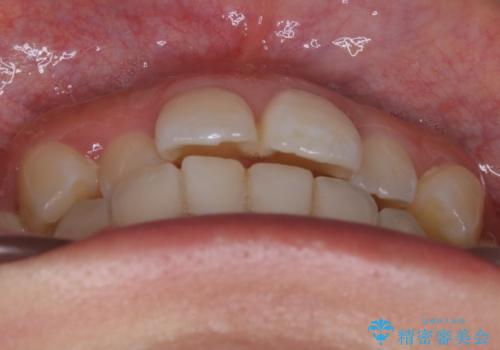

【非抜歯】部分矯正でも治る 前歯の反対咬合

- 前歯にガタつきを主訴にご来院されました。

奥歯の嚙み合わせに問題がほとんどみられなかったため、インビザライン ライトパッケージでの部分矯正を行うこととなりました。

今回のケースでは奥歯の噛み合わせに問題がほぼみられなかったため、前歯の位置のみに焦点を当て部分矯正を行いました。